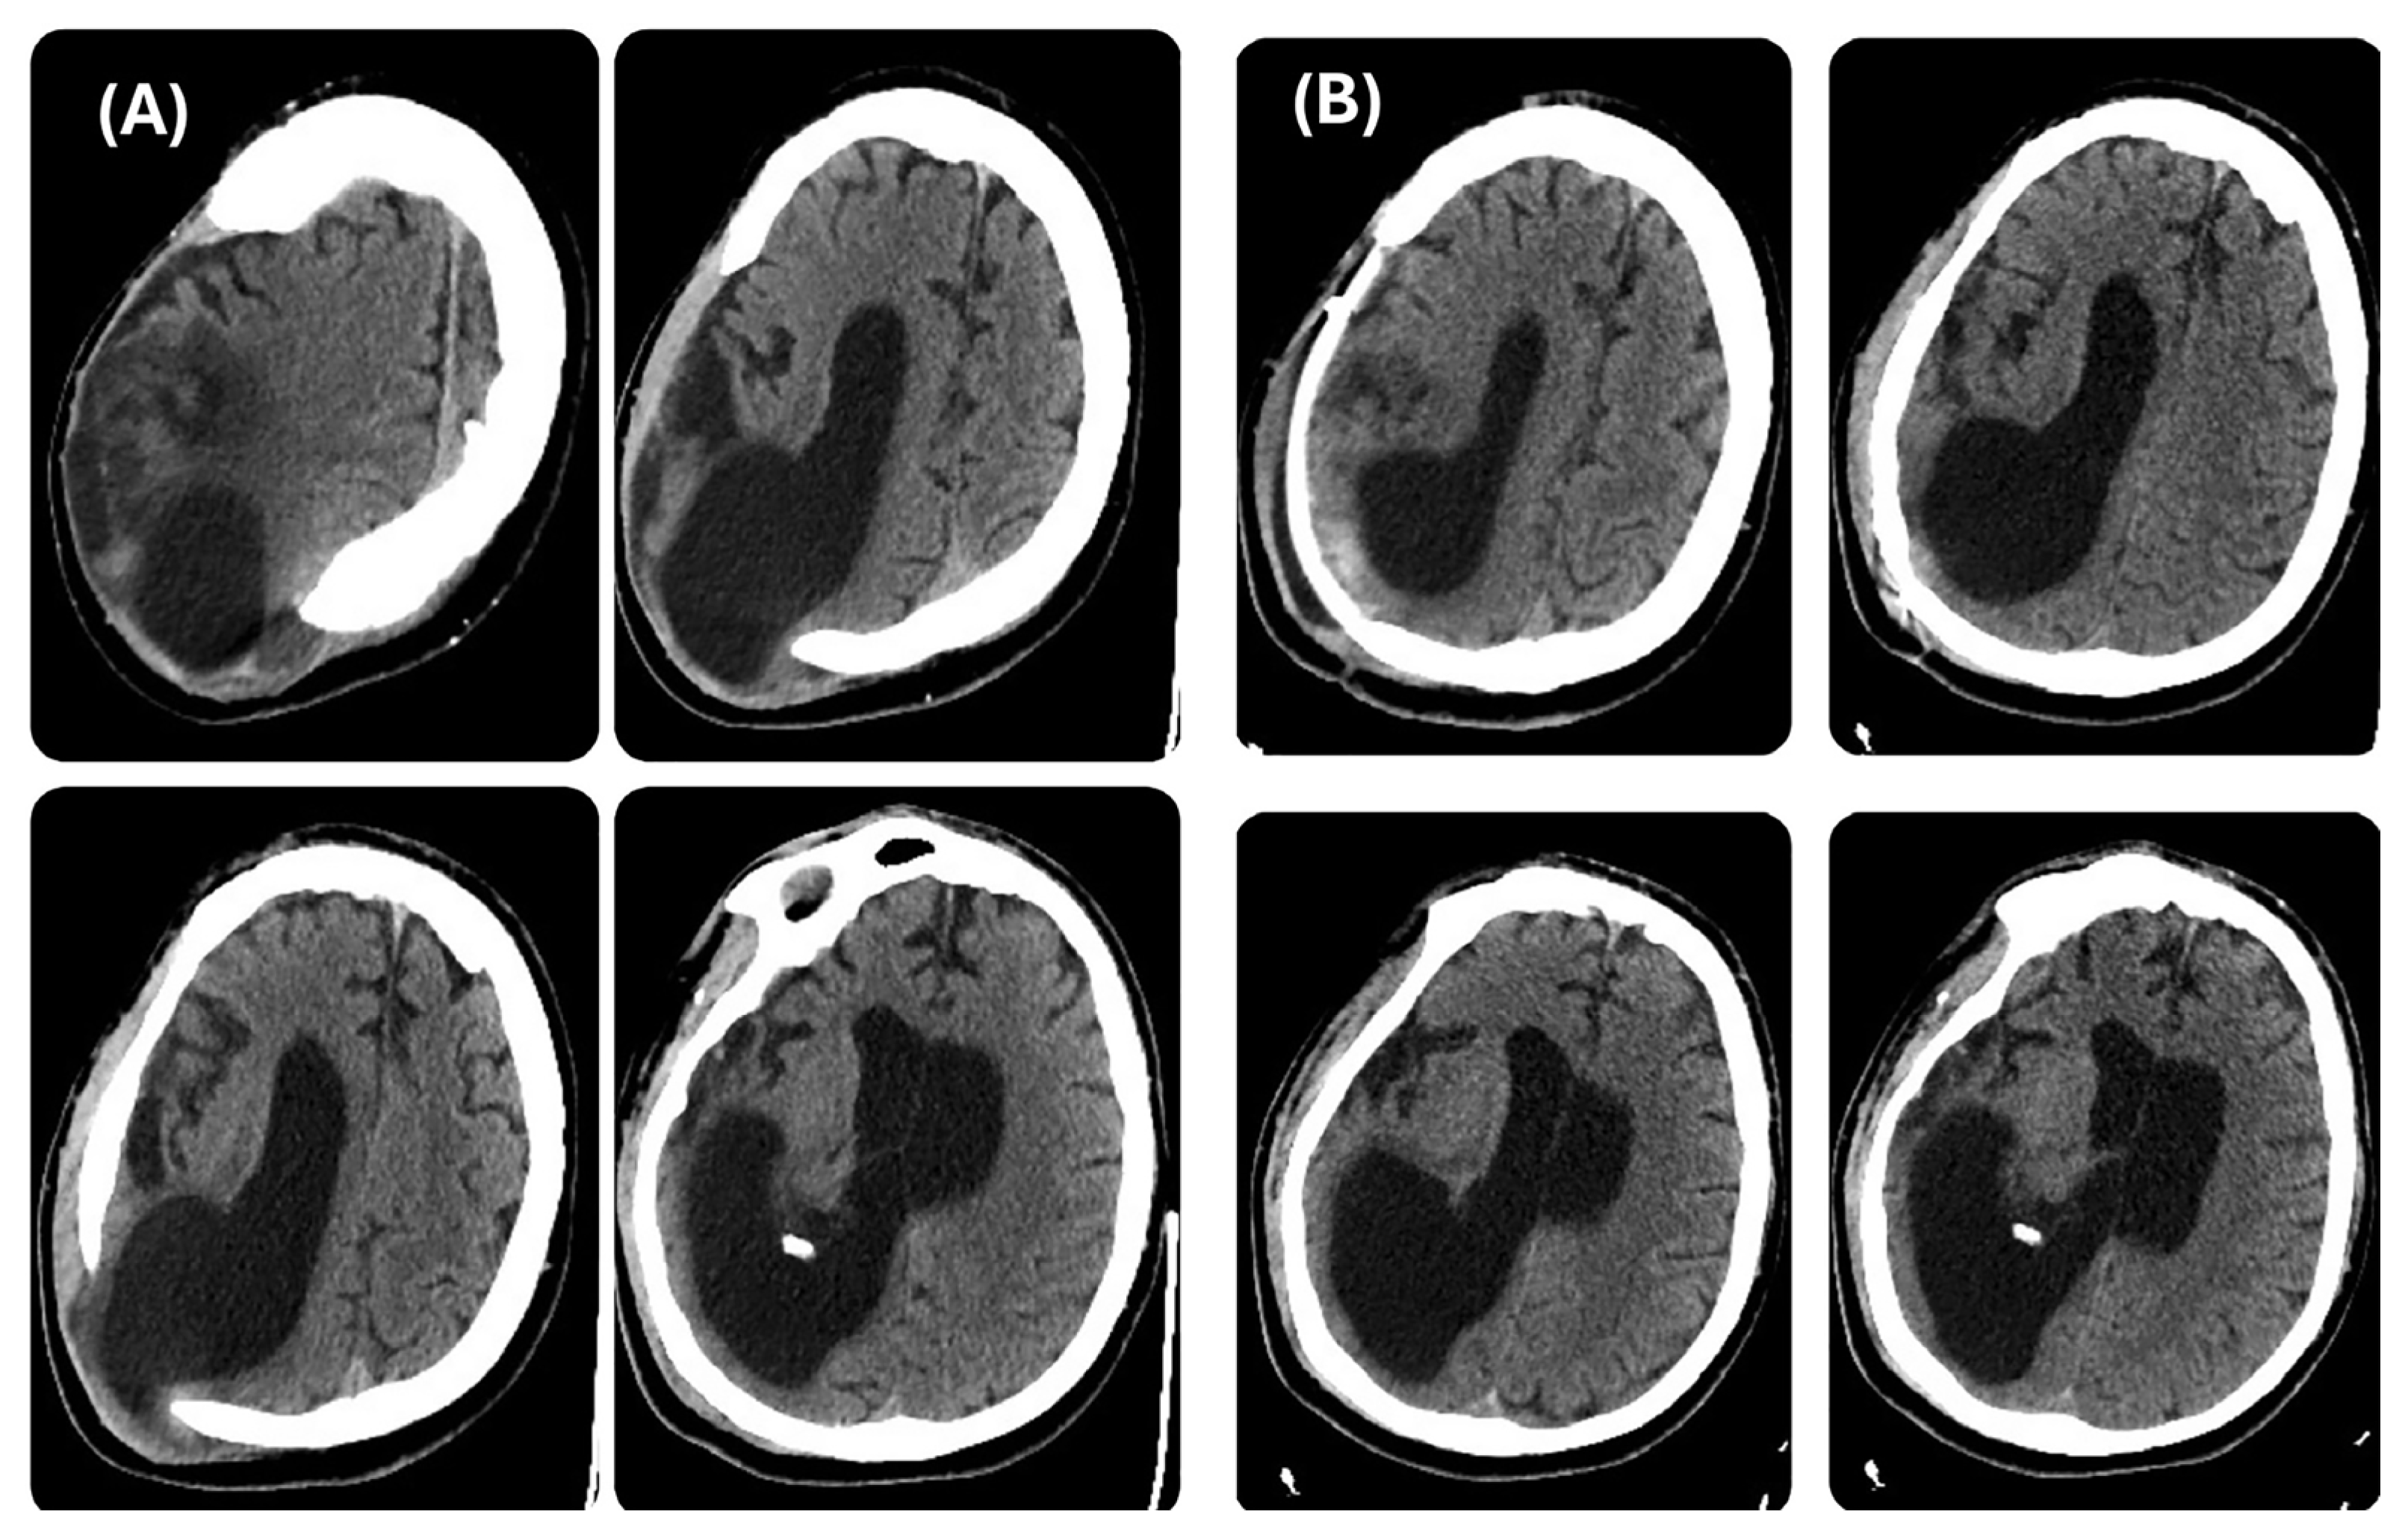

During his LTC stay, the patient was monitored with repeated CT scans. The last brain CT scan carried out before reconstructive CP (Figure 2A) showed further right occipital horn enlargement with persistence of protrusion of the brain parenchyma at the craniectomy site. One month after the CP, a CT scan was repeated, revealing patches of blood-like hyperdensity in the cortico-subcortical location corresponding to the posterior horn of the right lateral ventricle at the surgical site, with persistent significant right ventricle dilatation (Figure 2B).

Figure 2. Brain CT scan, axial view. Left side (A) before cranioplasty and right side (B) after cranioplasty.